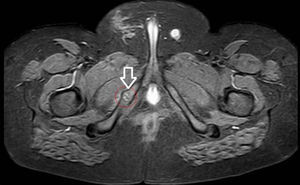

En la radiografía AP de pelvis (fig. 1) evidenció la SIP derecha aumentada de tamaño con pequeñas irregularidades de aspecto seudotumoral. En la RM (fig. 2) una imagen asimétrica e irregular, en «puente fibroso», que afecta a la sindesmosis isquiopubiana derecha (T1) y señal hiperintensa con edema de partes blandas asociado en secuencias T2 y STIR. Todo ello compatible con el diagnóstico de «osteocondritis de Van Neck-Odelberg».

En la radiología simple es habitual el aumento de la sincondrosis con áreas radiolúcidas y osteolíticas. Los hallazgos típicos de la RM incluyen cambios en la médula ósea y edema de partes blandas perilesionales2–4.